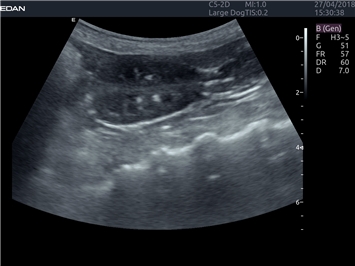

EDAN Acclarix LX4 VET

EDAN Acclarix LX4 VET представляет собой профессиональную ультразвуковую систему, специально разработанную для ветеринарных исследований. Сочетание стабильности, высокой производительности и эффективности делает эту систему идеальным выбором для современной ветеринарной практики.